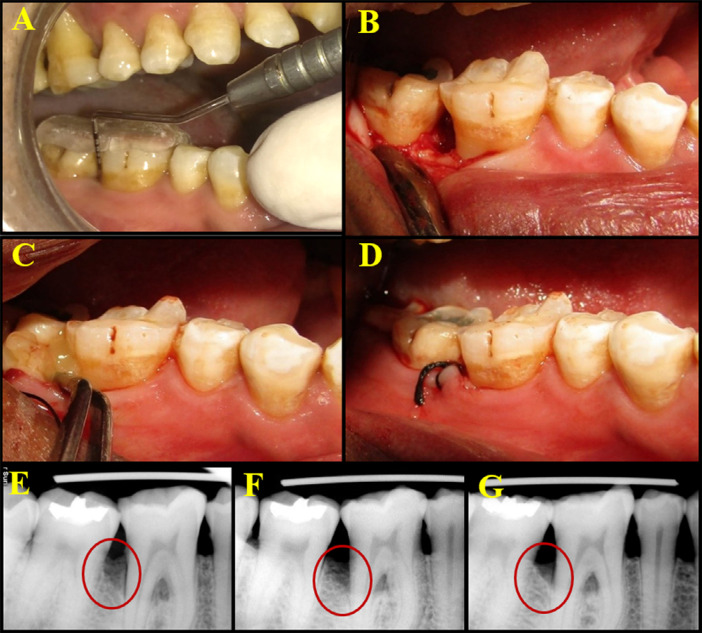

Methodology: This study included 17 patients of both sexes (12 men, 5 women) aged 30-55 years (mean age = 37.7±4.4 years) who fulfilled the inclusion criteria (radiographic and clinical evaluation for bilateral IOD with probing pocket depth (PPD ≥ 6 mm). A split-mouth design was used in each patient. A total of 34 sites in the mandibular arch randomly received PRFM alone + open flap debridement (OFD) [Control sites] or supercell (PRFM+PBMSCs) + OFD [Test sites]. The clinical parameters plaque index (PI), gingival index (GI), PPD, clinical attachment level (CAL), and in the radiographic parameters; defect depth (DD) and defect fill percentage (DFP) were recorded at baseline, 3 and 6 months postoperatively. Early wound healing index (EHI) was used at 1 week to assess wound healing ability.

Results: At 6 months, radiographic parameters revealed significant reduction in DD (P<0.001) and significant DFP values in the test group compared with the control group. The supercell showed significant improvement in PPD and CAL at the end of 6 months (P<0.001). EHI scores at 1 week showed no statistically significant difference between the test and control groups.